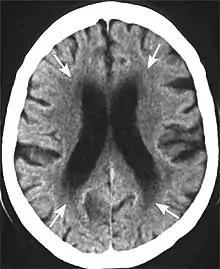

Head CT showing periventricular white matter lesions.

The blue arrows indicate leucoaraiosis. In the left image these may well represent transependymal CSF diapedesis due to normal pressure hydrocephalus, which in turn is suggested by the narrowed superior CSF spaces and acute callosal angle. The unilateral occurrence of these alterations in right image suggests they are probably due to vascular encephalopathy.